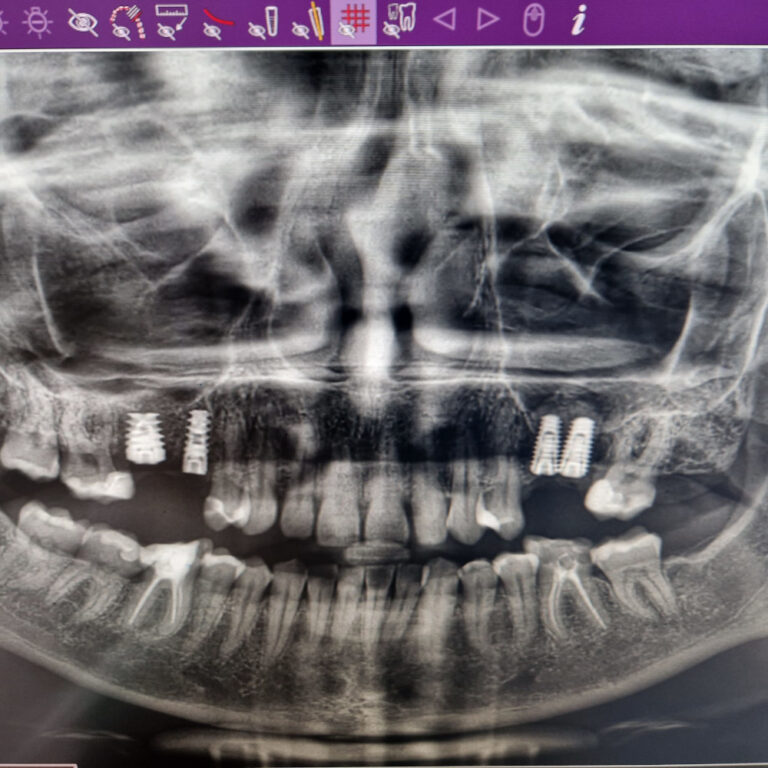

Implanty zygomatyczne

Przykłady implantologii

Zastosowanie implantoprotetyki w przypadku gdy klasyczna protetyka nie sprawdza się.